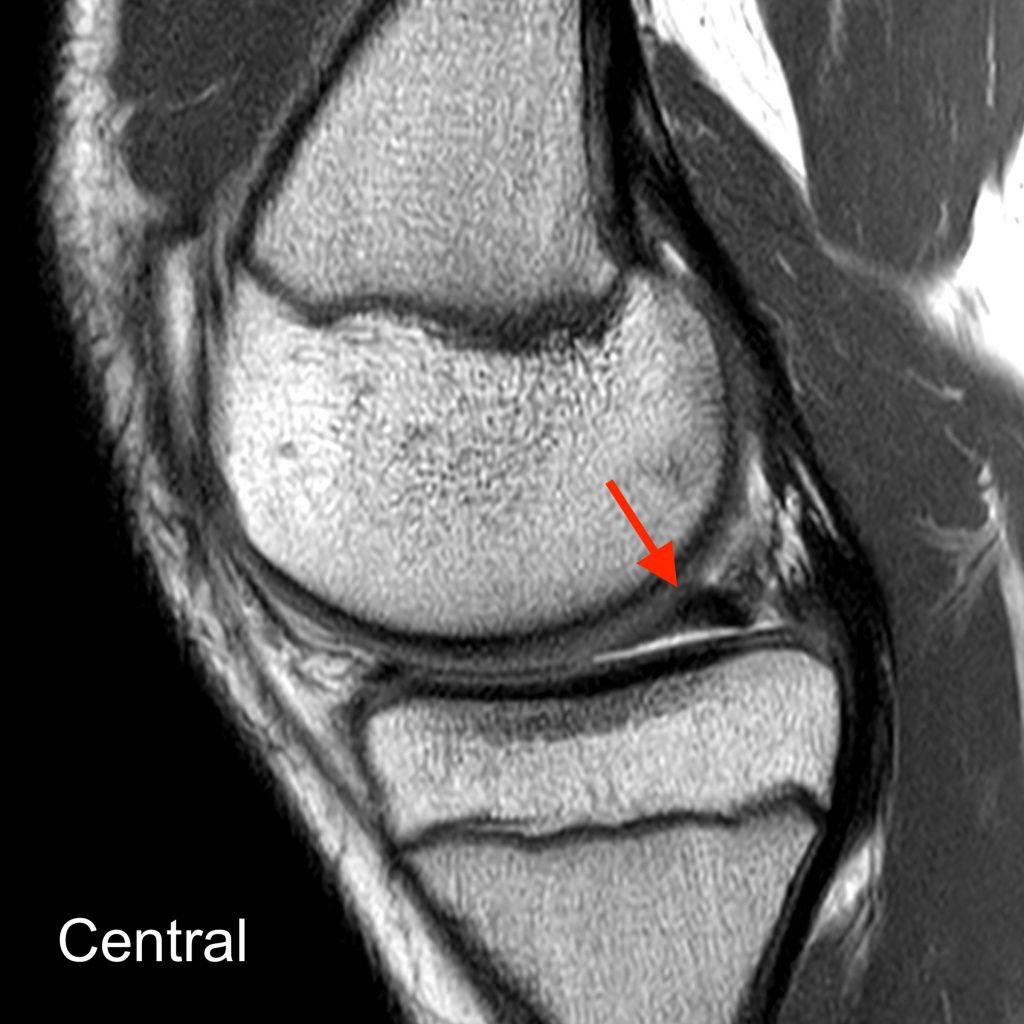

Buckethandle Tear of the Meniscus Radsource

From radsource.us

From mrionline.com